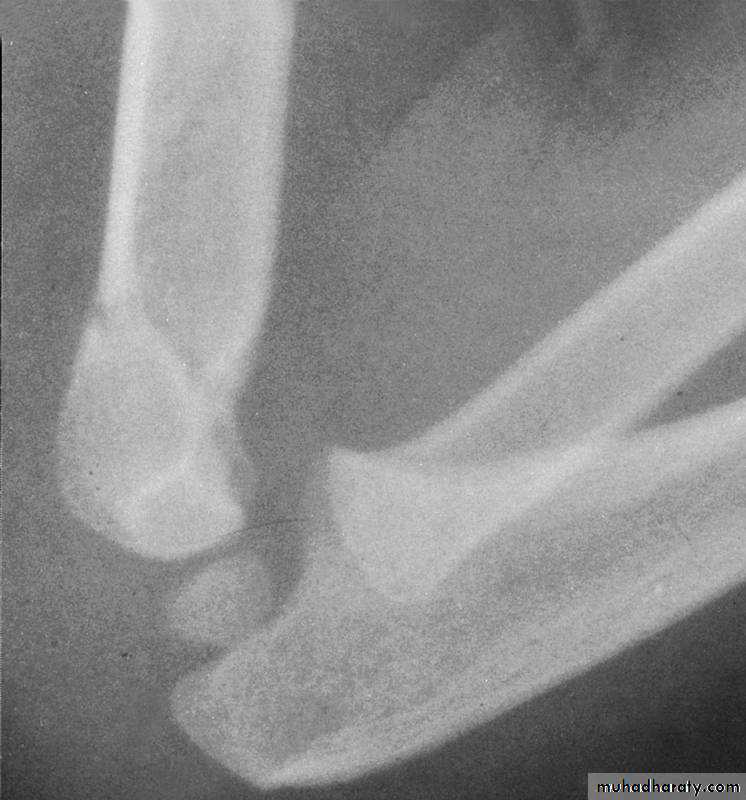

fractures?How are Type III extension supracondylar

fractures sub-classified?Yes

Posteromedial vs. Posterolateral

Reduction of the fractureWhat does the manipulative

process entail ?

With the elbow in extension, align the distal fragment

to the proximal fragment in the coronal plane.1. Correct coronal plane alignment

2. Re-establish Length

TractionCounter-Traction

3.Correct Angulation

andPosterior Displacement

Apply longitudinal traction

with the elbow semi- flexed,while applying posterior

pressure on the proximal fragment.

Then, slowly flex the elbow to bring

the distal fragment into alignment.4. Temporary stabilization and assessment